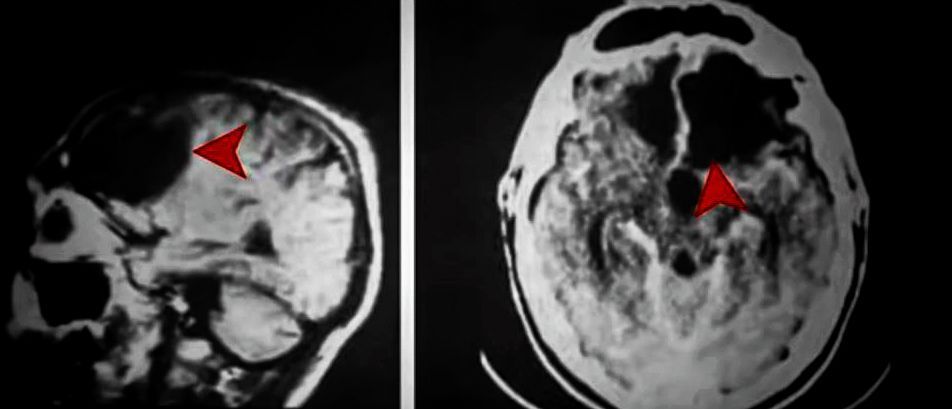

El paciente Elliot, de 35 años, se había sometido a la extirpación de un peligroso tumor cerebral justo en las estructuras que son necesarias para que el razonamiento culmine en la toma de decisiones. Dichas estructuras eran los lóbulos frontales.

Damasio expuso entonces la importancia que tiene el córtex orbitofrontal exponiéndolo en su libro “El error de Descartes” en el que concluye que, solo cuando conectamos los sentimientos con el pensamiento consciente podemos tomar decisiones.